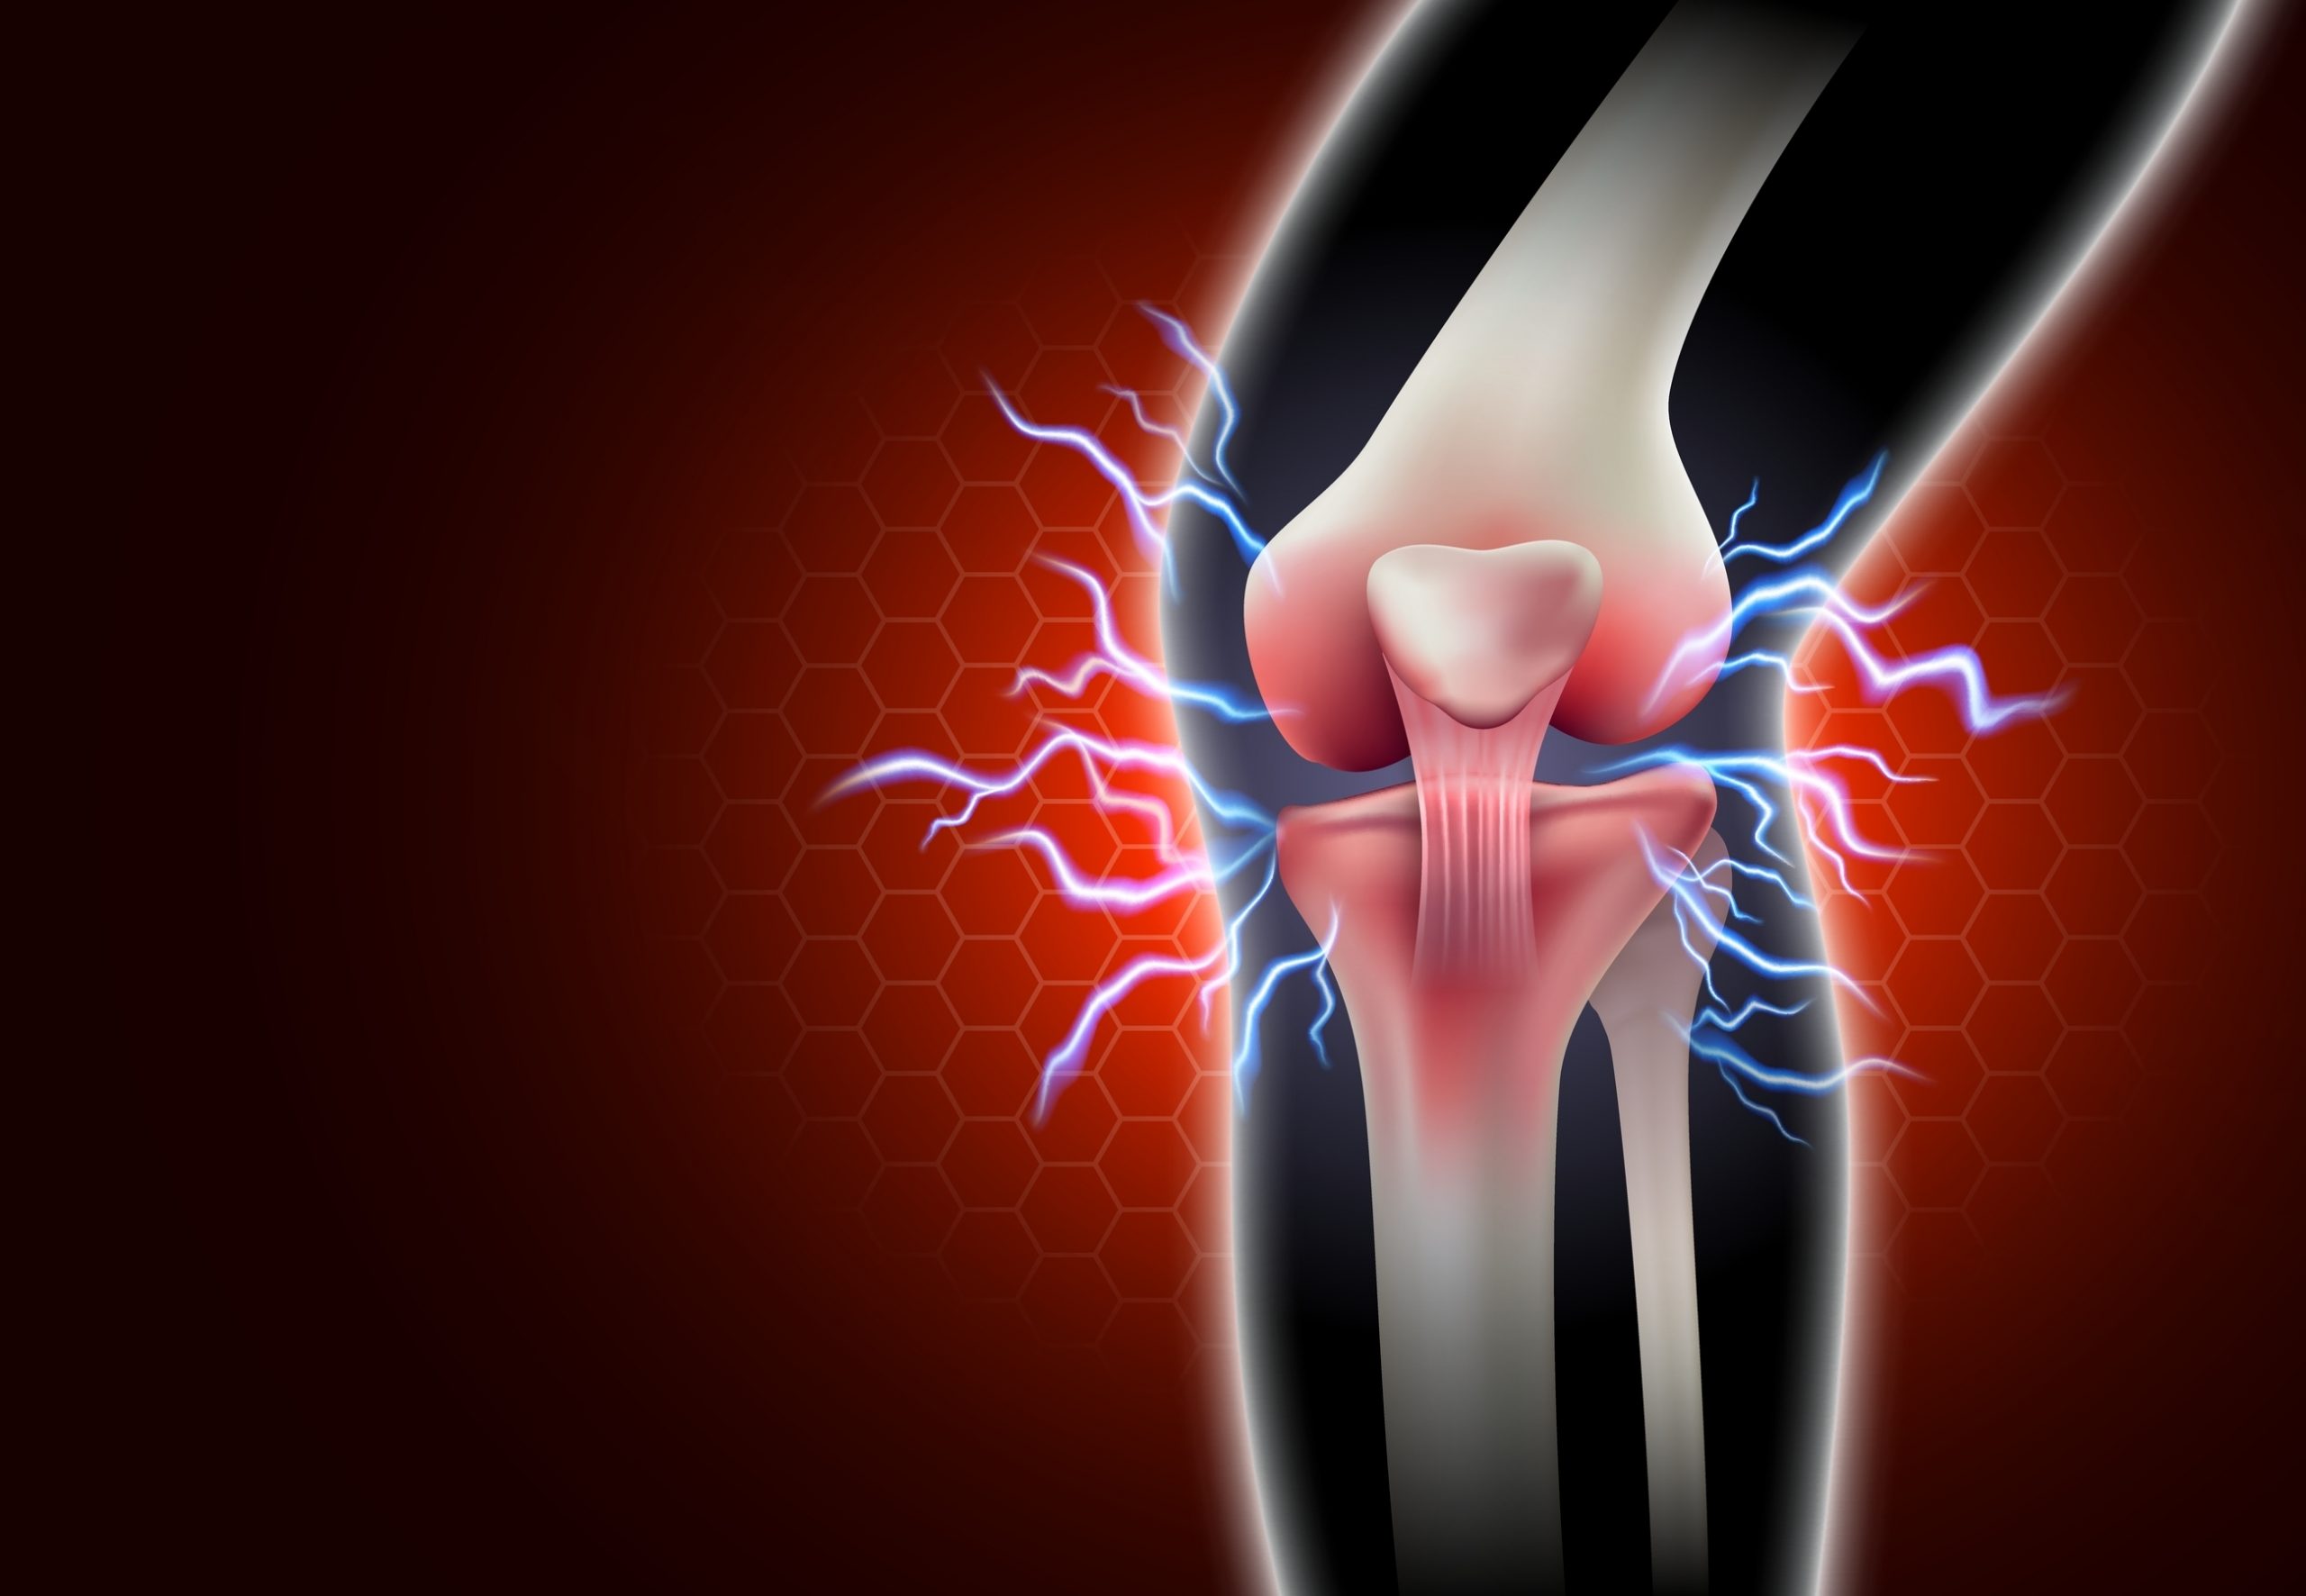

Ból stawów – jakie badania autoimmunologiczne?

Ból stawów może mieć różne przyczyny, ale jeśli jest przewlekły, towarzyszy mu sztywność i obrzęk, warto zbadać, czy jego źródłem nie jest choroba autoimmunologiczna. Choroby autoimmunologiczne to schorzenia, w których układ odpornościowy atakuje zdrowe tkanki, w tym stawy, co prowadzi do stanu zapalnego i bólu. W tym artykule dowiesz się, jakie badania warto wykonać, aby zdiagnozować autoimmunologiczne przyczyny bólu stawów.